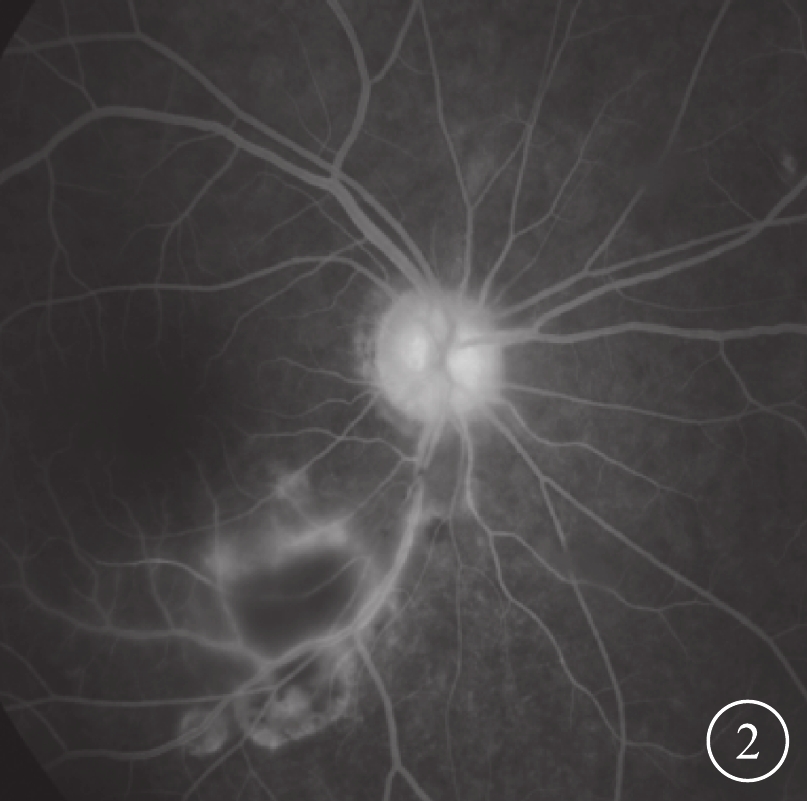

行FFA檢查的6只眼,陳舊病灶早期呈弱熒光,晚期不同程度及范圍熒光著染;新病灶早期呈熒光遮蔽,晚期表現為邊緣熒光著染,中央病灶遮蔽或不同程度的熒光著染。其中,伴視網膜靜脈擴張、紆曲、管壁著染及滲漏4只眼;視網膜動脈階段性白線樣改變(圖2)2只眼,病變血管區無明顯滲漏,但仍有灌注,其中出現在活動性病變區視網膜動脈1只眼,其他區域視網膜動脈1只眼。